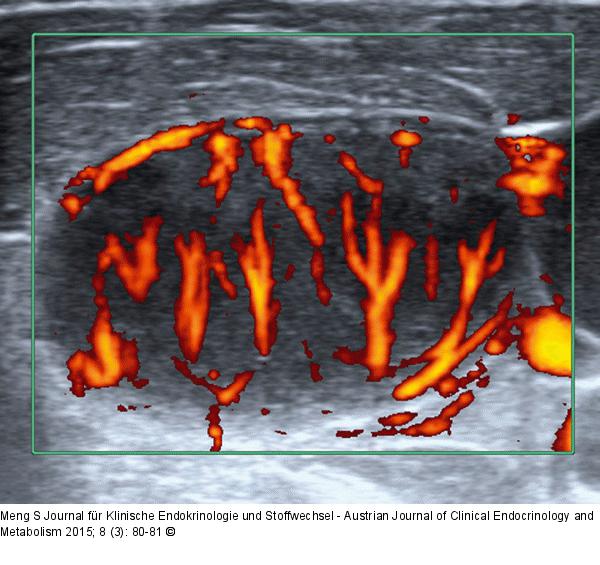

Abbildung 2: Lymphknoten-Ultraschall Pathologische Gefäßarchitektur. In diesem Fall sind mehrere Ausgangspunkte für Gefäßbäume zu erkennen. Starke Flowsignale sind auch in der Peripherie des Cortex zu erkennen. Lymphom (DLBCL) |

Pathologische Gefäßarchitektur. In diesem Fall sind mehrere Ausgangspunkte für Gefäßbäume zu erkennen. Starke Flowsignale sind auch in der Peripherie des Cortex zu erkennen. Lymphom (DLBCL) |